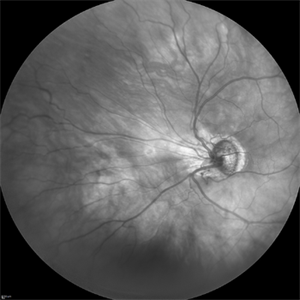

ROP stage 3

Sep 22 2022 by Filip Kecer

IR cSLO widefield image of an 27-year-old man born as premature

Photographer: Filip Kecer, National Institute of Childrens Diseases

Imaging device: Spectralis, Heidelberg Engineering

Condition/keywords: retinopathy of prematurity stage 3, rop